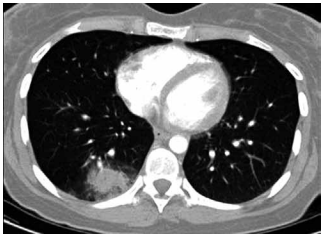

Mulher de 31 anos, recentemente diagnosticada com

leucemia mieloide aguda, é internada com neutropenia

febril doze dias após o primeiro ciclo de quimioterapia de

consolidação com citarabina em altas doses. Ela é tratada adequadamente com cefepima intravenosa. Sete

dias após, as hemoculturas são negativas e a contagem

de leucócitos está começando a se recuperar. Ela agora

apresenta febre de 38 °C, tosse e desconforto torácico

pleurítico. Os níveis séricos de galactomanana e beta-glucana estão elevados. A tomografia de tórax realizada

agora é mostrada a seguir:

(Arquivo pessoal; imagem usada com autorização)

Com maior probabilidade, o diagnóstico é de